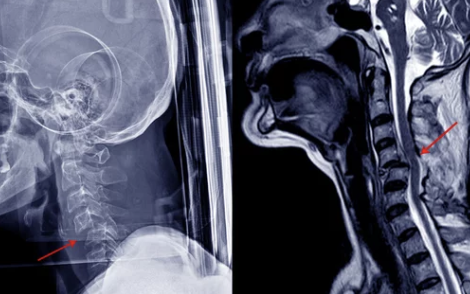

목디스크는 목뼈 사이에 위치한 디스크가 압박을 받아 탈출하거나 손상되어 발생하는 질환이에요. 디스크가 탈출하면서 신경을 누르게 되어 통증과 다양한 증상이 나타납니다.

4. 목디스크 진단과 치료법: 비수술적 치료부터 수술까지

목디스크가 의심되면 정확한 진단을 통해 치료 방법을 결정해야 해요. 요즘은 비수술적 치료법이 많이 발달해 있어 초기에는 수술 없이 치료가 가능해요.